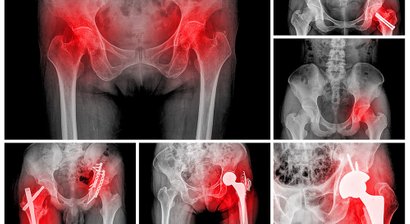

Ich und mein Team arbeiten nach modernsten wissenschaftlichen Erkenntnissen und nutzen sämtliche bewährte Abklärungsmethoden, um Ihrem Bewegungsschmerz und dessen Ursache auf die Spur zu kommen. So verfügt die Praxis u.a. über ein hochmodernes, digitales Spezialröntgen zur genauen Abklärung und Diagnosefindung.